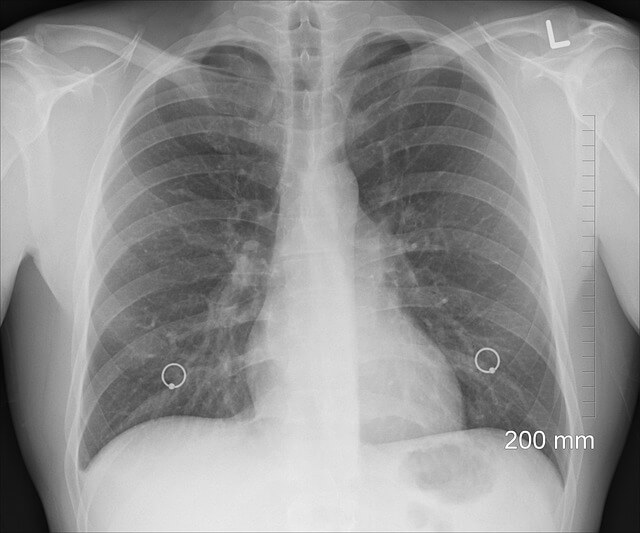

흉부 X-ray 또는 CT 스캔

폐렴의 증상과 의심되는 경우 의사는 흉부 X-ray 또는 CT 스캔을 요청할 수 잇습니다. 이를 통해 폐의 염증과 증상의 정도를 시작적으로 확인할 수 있습니다. X-ray는 초기 진단에 유용하며, CT 스캔은 더 세부적인 정보를 제공합니다. 폐렴에 의한 염증, 액체 축척, 기타 폐 손상을 보다 자세히 확인할 수 있습니다.